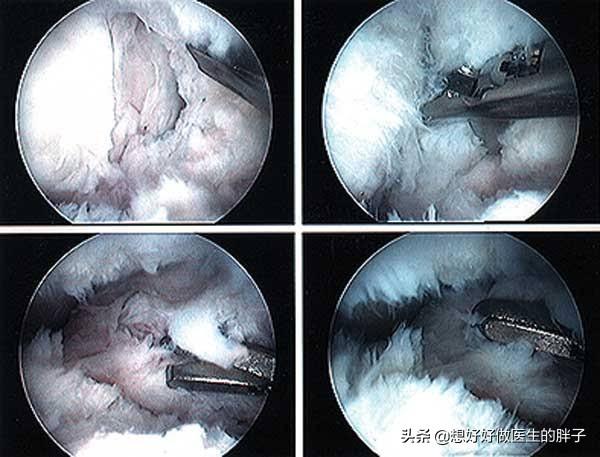

这是由于在训练的当天经过康复锻炼将粘连的索条会有一定的撕裂,关节活动自然会有一定的增加。但是经过一夜的休息以后,这种撕裂的部分又再次愈合了,所以次日角度又恢复如常了。大家看下图,关节镜手术当中这些像纤维一样在关节静镜下飘舞的结构,就是关节腔内大量的粘连。